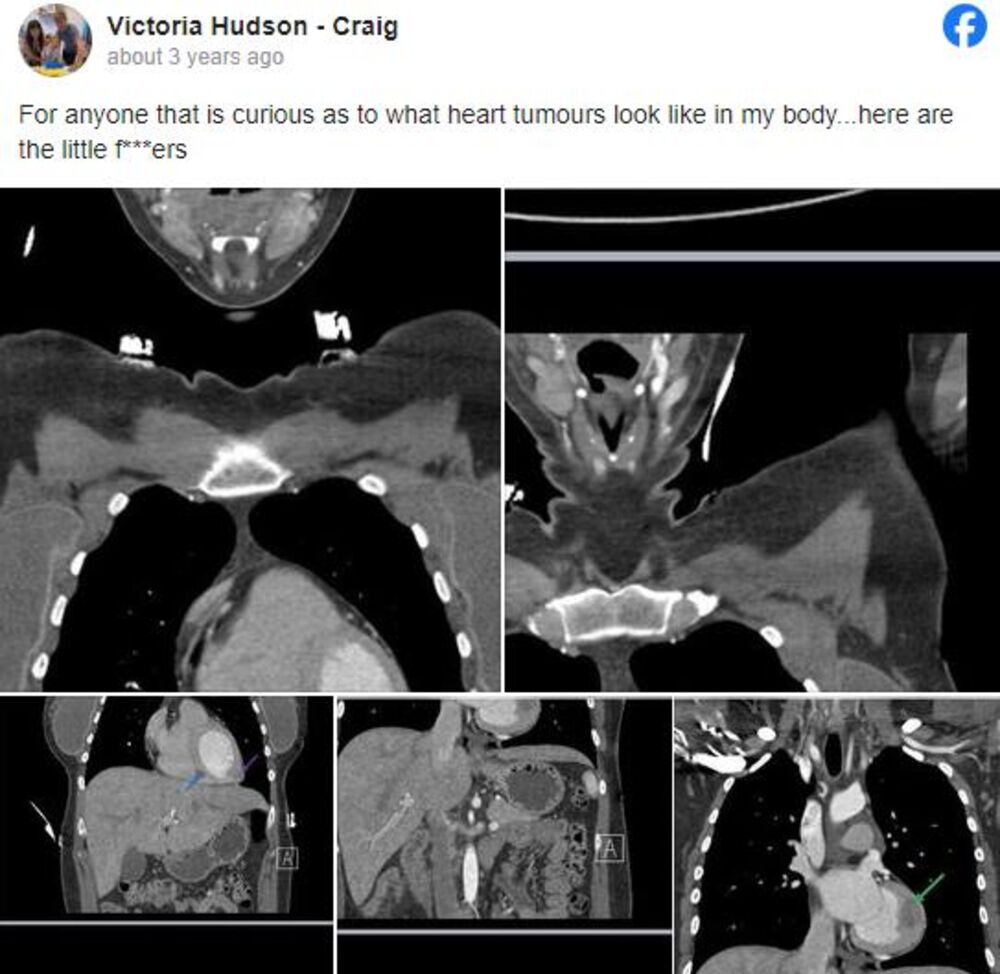

Viktorija se 2015. preselila na Novi Zeland, upoznala supruga i rodila ćerku Rubi 2017. Tri godine kasnije, u oktobru 2020. osetila je oštar bol u stomaku i hitno je prebačena u bolnicu sa upalom slepog creva. Ali, snimci su pokazali da stvar nije u slepom crevu, već u dva tumora na srcu.

Viktorija se prisetila doktorovog izraza šoka. Nekoliko testova kasnije, njoj su dijagnostikovana četiri tumora na srcu - tri oko dna mišića i jedan u sredini.

- Rak je napredovao, a lekari su takođe pronašli peti tumor u mom srcu u decembru 2021. Nedelju dana pre Božića, doktori su mi rekli da je svih pet tumora naraslo, a da je najveći bio šest centimetara.